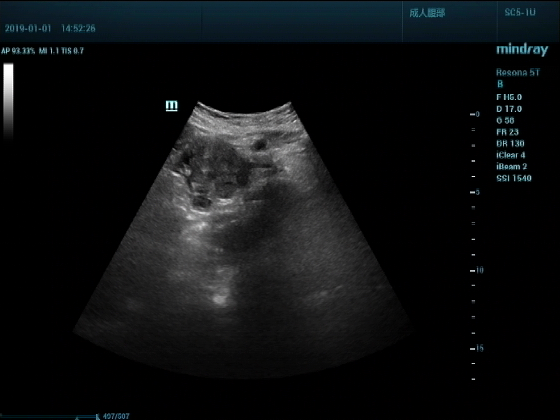

超声入门贴959--胰头癌并胰管扩张

男,88岁,腹部隐疼2个月加重3天来诊